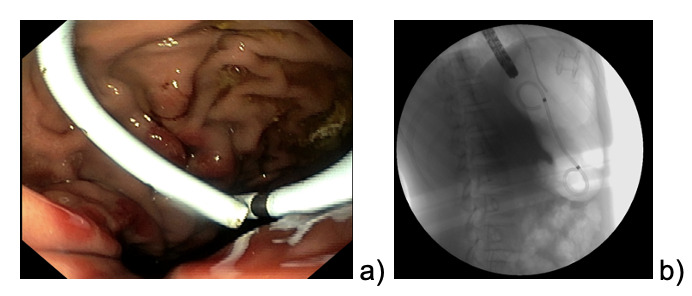

The patient continued to refer mild abdominal pain, and a cholangio MRI confirmed the persistency of an encapsulated pancreatic fluid collection without size reduction (Fig.1b). After a multidisciplinary discussion, the decision was made to perform an endoscopic-ultrasound (EUS) guided cystogastrostomy with a 10 x 10 mm lumen-apposing metal stent (LAMS) (Hot-Axios™ system) under general anesthesia. During the procedure, after the release of the LAMS, a 7 cm x 7 Fr double-pigtail plastic stent (DPPS) was coaxially released (Fig.2); the post-operative course was uneventful and the patient was discharged after 48 hours. Seven days thereafter, an abdominal ultrasound confirmed the complete resolution of the PCF, the LAMS was removed, and a “soft” DPPS 7 cm x 10 Fr (Solus-Cook®) was positioned endoscopically in the cystic cavity under endoscopic and radiological control (Fig.3). The patient was dismissed the following day without any complications, and two weeks thereafter she restarted the AIEOP-BFM-2017 protocol at Short Consolidation B, 4 months after the interruption of the consolidation phase. No pancreatic fluid collection was observed at the following abdominal ultrasounds, the latest performed 7 months after interventions, together with an abdominal x-ray that showed the persistent presence of the double pig-tail. The prosthesis removal will be scheduled together with the central venous catheter removal at the end of the maintenance phase, due in a few months, so as to perform a single sedation.

_echoendoscopy__b-c)_stent_placement.png)

_dpps_positioning__b)_radiological_control.png)